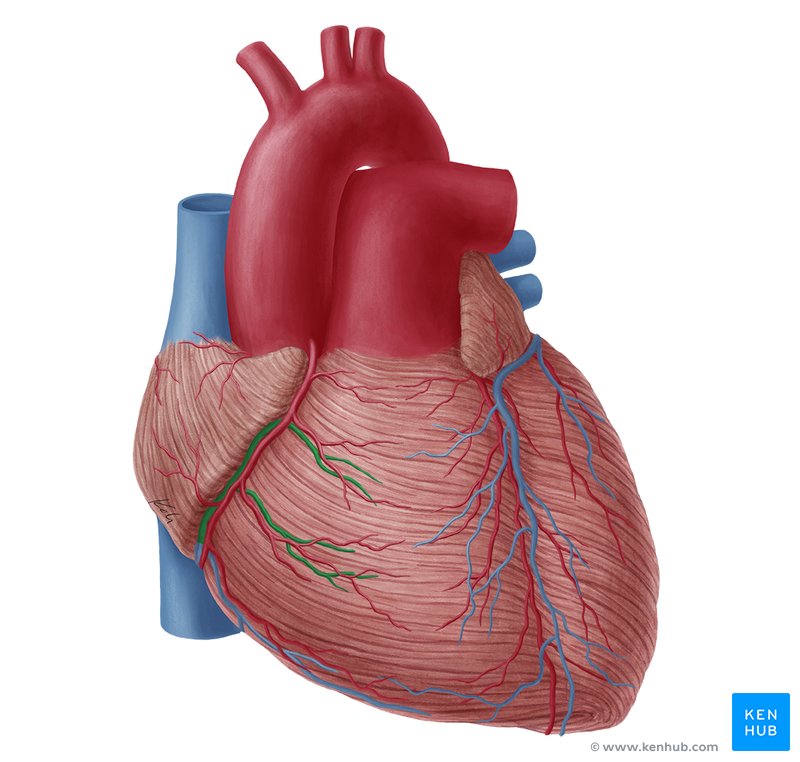

Anterior Interventricular Artery

Circumflex Branch

Coronary Artery

Coronary Sinus

Anterior Interventricular Sulcus

Coronary Sulcus

Small Cardiac Vein

Anterior Cardiac Vein

Posterior Interventricular Sulcus/Artery

Marginal Branch

Circumflex Artery

Great Cardiac Vein